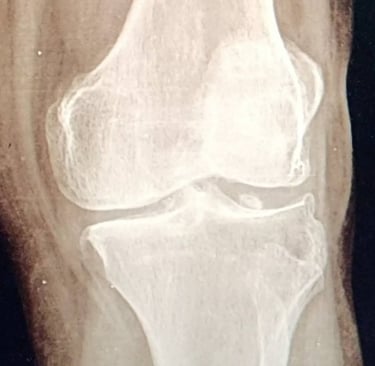

Para identificar la causa del dolor, el especialista realiza una evaluación clínica completa, revisando la movilidad de la rodilla, la estabilidad de los ligamentos y los puntos específicos de dolor.

En muchos casos se solicitan estudios de imagen, como radiografías, ultrasonido o resonancia magnética, que permiten evaluar las estructuras internas de la articulación y confirmar el diagnóstico.